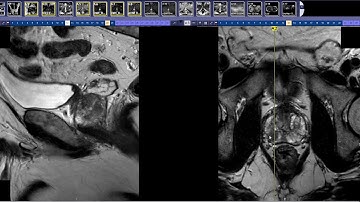

Introduction to Prostate MRI and PI-RADS: Approach and Principles